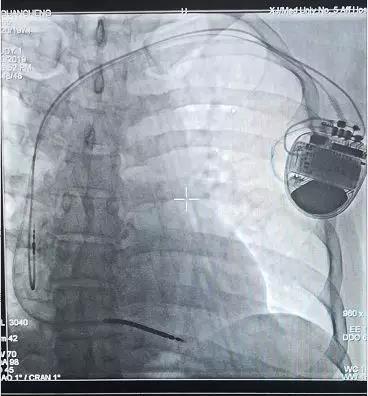

主管大夫张颖主治医师迅速安排了相关检查,完善评估后,老付被确诊患有冠状动脉粥样硬化型心脏病、陈旧性下后壁心肌梗死、缺血性心肌病、心律失常、阵发性室速等疾病。患者心脏超声提示EF值不到35%,随时可能出现室性心动过速、室颤等恶性心律失常,甚至猝死,必须及早植入ICD。3月20日幸世峰、麦麦提阿卜杜拉为老付实施了埋藏式心律转复除颤器植入术,术前、术中老付一直非常紧张,幸世峰不时安慰老付,手术很顺利,历时四十分钟,测试各项参数非常理想。手术结束时老付和家人悬在心头的一块大石头终于落地,看到手术大夫,眼中充满了感激。